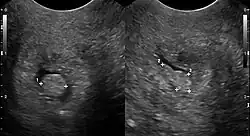

| Cervical polyp on ultrasound | |

Cervical polyps can be seen during a pelvic examination as red or purple projections from the cervical canal.[4] Diagnosis can be confirmed by a cervical biopsy which will reveal the nature of the cells present.[4]